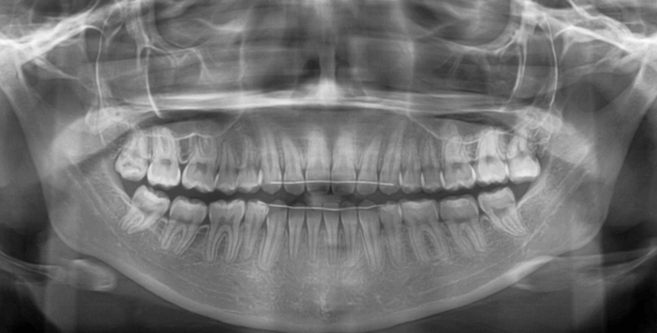

咬み合わせが逆であること(反対咬合)が気になる

| 年齢・性別 | 15歳 女性 |

|---|---|

| 主訴 | 咬み合わせが逆であること(反対咬合)を気にされて来院された女性。見た目や機能面の改善を希望されていました。 |

| 治療期間・回数 | 4年4ヶ月・28回 |

| 費用 | 900,000円 |